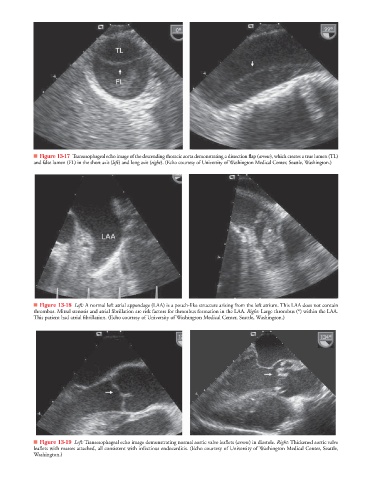

■ Figure 13-17 Transesophageal echo image of the descending thoracic aorta demonstrating a dissection flap (arrow), which creates a true lumen (TL)w

and false lumen (FL) in the short axis (left) and long axis (right). (Echo courtesy of University of Washington Medical Center, Seattle, Washington.)

■ Figure 13-18 Left: A normal left atrial appendage (LAA) is a pouch-like structure arising from the left atrium. This LAA does not contain

thrombus. Mitral stenosis and atrial fibrillation are risk factors for thrombus formation in the LAA. Right: Large thrombus (*) within the LAA.

This patient had atrial fibrillation. (Echo courtesy of University of Washington Medical Center, Seattle, Washington.)

■ Figure 13-19 Left: Transesophageal echo image demonstrating normal aortic valve leaflets (arrow) in diastole. Right: Thickened aortic valve

leaflets with masses attached, all consistent with infectious endocarditis. (Echo courtesy of University of Washington Medical Center, Seattle,

Washington.)